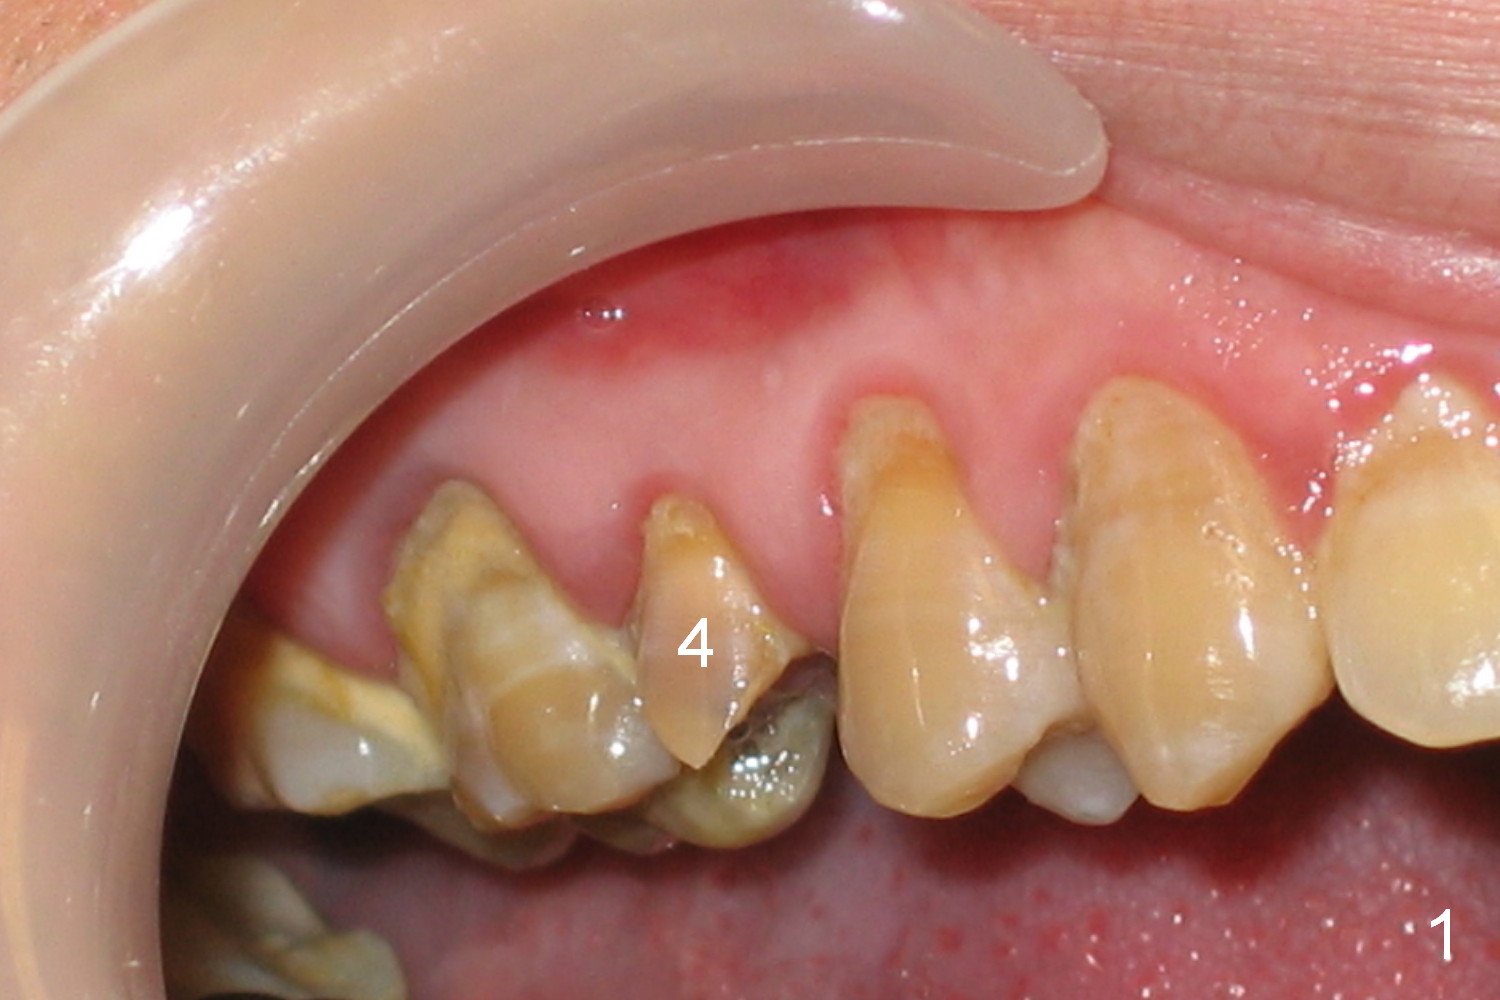

ZC is a 36-year-old man without significant medical history. His chief complaint is "I have Pain sometimes". His oral hygiene is poor (Fig.1). The tooth #3 has large MO caries with periapical radiolucency (*). The tooth #4 is non-salvageable (Fig.1,2). Four months after scaling & root planing, RCT and crown for #3 and extraction of #4 (Fig.3), a 5x8 mm Bicon implant is placed at the site of #4 (Fig.4). Peri-implant space is obliterated 5 months postop (Fig.5). The 2nd surgery is performed to uncover the implant and to place a temporary abutment. Two weeks later, a 5.0x.3.0 mm 0 degree Stealth Abutment 3.0 mm Post is placed (Fig.6). The most recent recall PA shows no bone loss for 5 years 3 months post cementation (Fig.7).